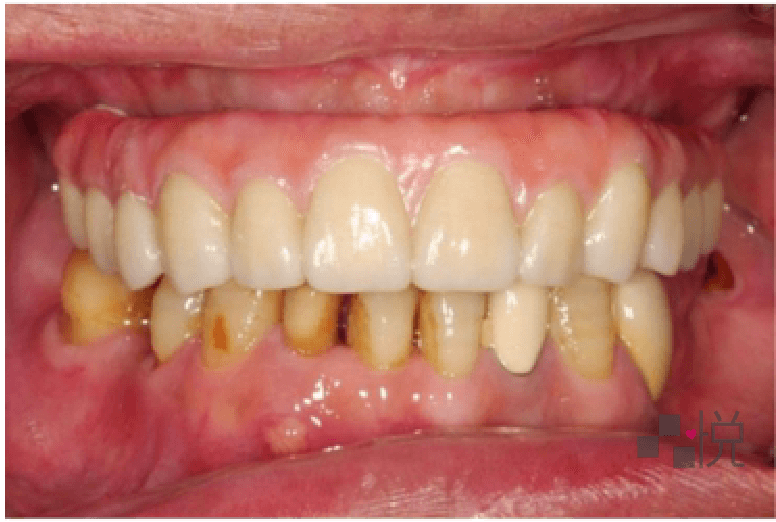

由於本來的缺損太嚴重,最終假牙部分則採用陶瓷假牙肉來模擬真牙,並搭配多種不同的假牙形式,歷時一年多,終於重建進食功能及笑容,讓全院所的醫護都相當欣慰。

饒醫師最後想提醒讀者們,定期檢查很重要,小問題及時處理是最好的,如果想著牙齒痛了再處理,往往問題已經很嚴重了。